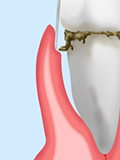

歯周ポケットがより深くなり、歯を支える顎の骨が溶け始めています。

歯ぐきのはれや出血が増して歯を指で押すと少しグラグラし、口臭も発生します。